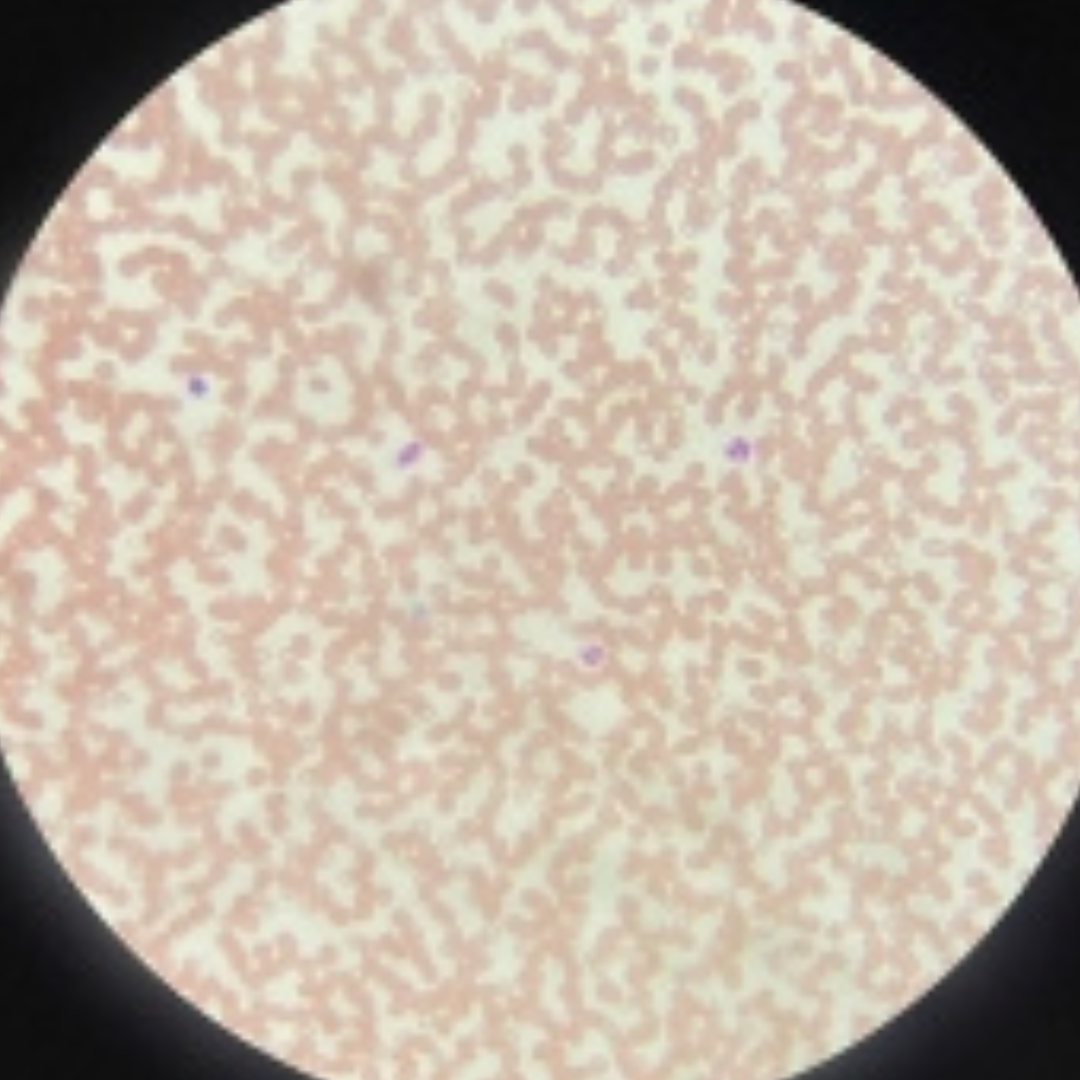

Bone Marrow

Bone Marrow